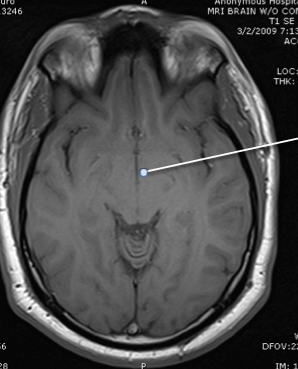

amygdala

hypothalamus

hippocampus

third ventricle

lateral ventricle